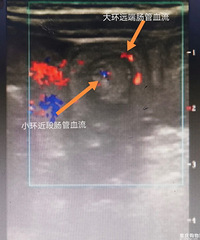

【千万小心!】来自深圳市儿童医院医生的忠告: “千万不要建议黄疸的新生儿去晒太阳…… 新生儿黄疸,虽然很常见,足月儿发生率大概50%,早产儿70%。 但有轻有重,轻者无需治疗,可自愈。重者,数小时内就变成脑病,并且一旦脑病,终身痴呆、瘫痪甚至快速死亡。